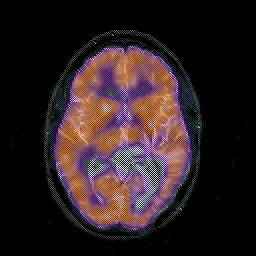

Glioblastoma multiforme overlay -- Slice #27

[Home][Help][Clinical][Tour 1][Tour 2][Tour 3] Slice 27